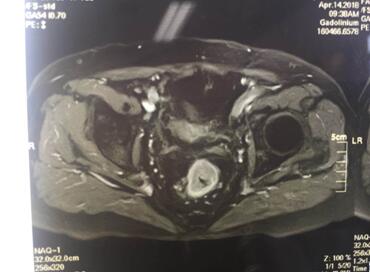

入院后譚曙光主任帶領(lǐng)賀賽奇副主任、周高副主任醫(yī)師及周平主治醫(yī)師等科室業(yè)務(wù)骨干為汪老制定詳細(xì)診療計(jì)劃。術(shù)前盆腔MRI及腸鏡、病理診斷考慮低位直腸腺癌(T3aN0M0)。鑒于汪老年老體弱,病變位置低,基礎(chǔ)疾病多,耐受力較差,譚主任及其手術(shù)團(tuán)隊(duì)精益求精,不斷完善診療措施,術(shù)前采取MDT(多學(xué)科合作)模式,于4月18日在全麻腹腔鏡下行直腸癌根治術(shù)+D3淋巴結(jié)清掃術(shù)+粘連松解,手術(shù)順利,術(shù)中徹底松解腹腔內(nèi)粘連,標(biāo)準(zhǔn)的TME(直腸全系膜切除)及D3淋巴結(jié)清掃,腹腔鏡下吻合口加固縫合,手術(shù)出血僅30ml,在原有的手術(shù)切口處取出手術(shù)標(biāo)本。